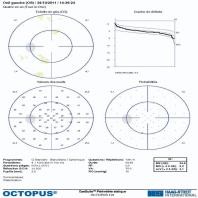

- eFig. 9-18 - Relevé de test de seuil N-30-F